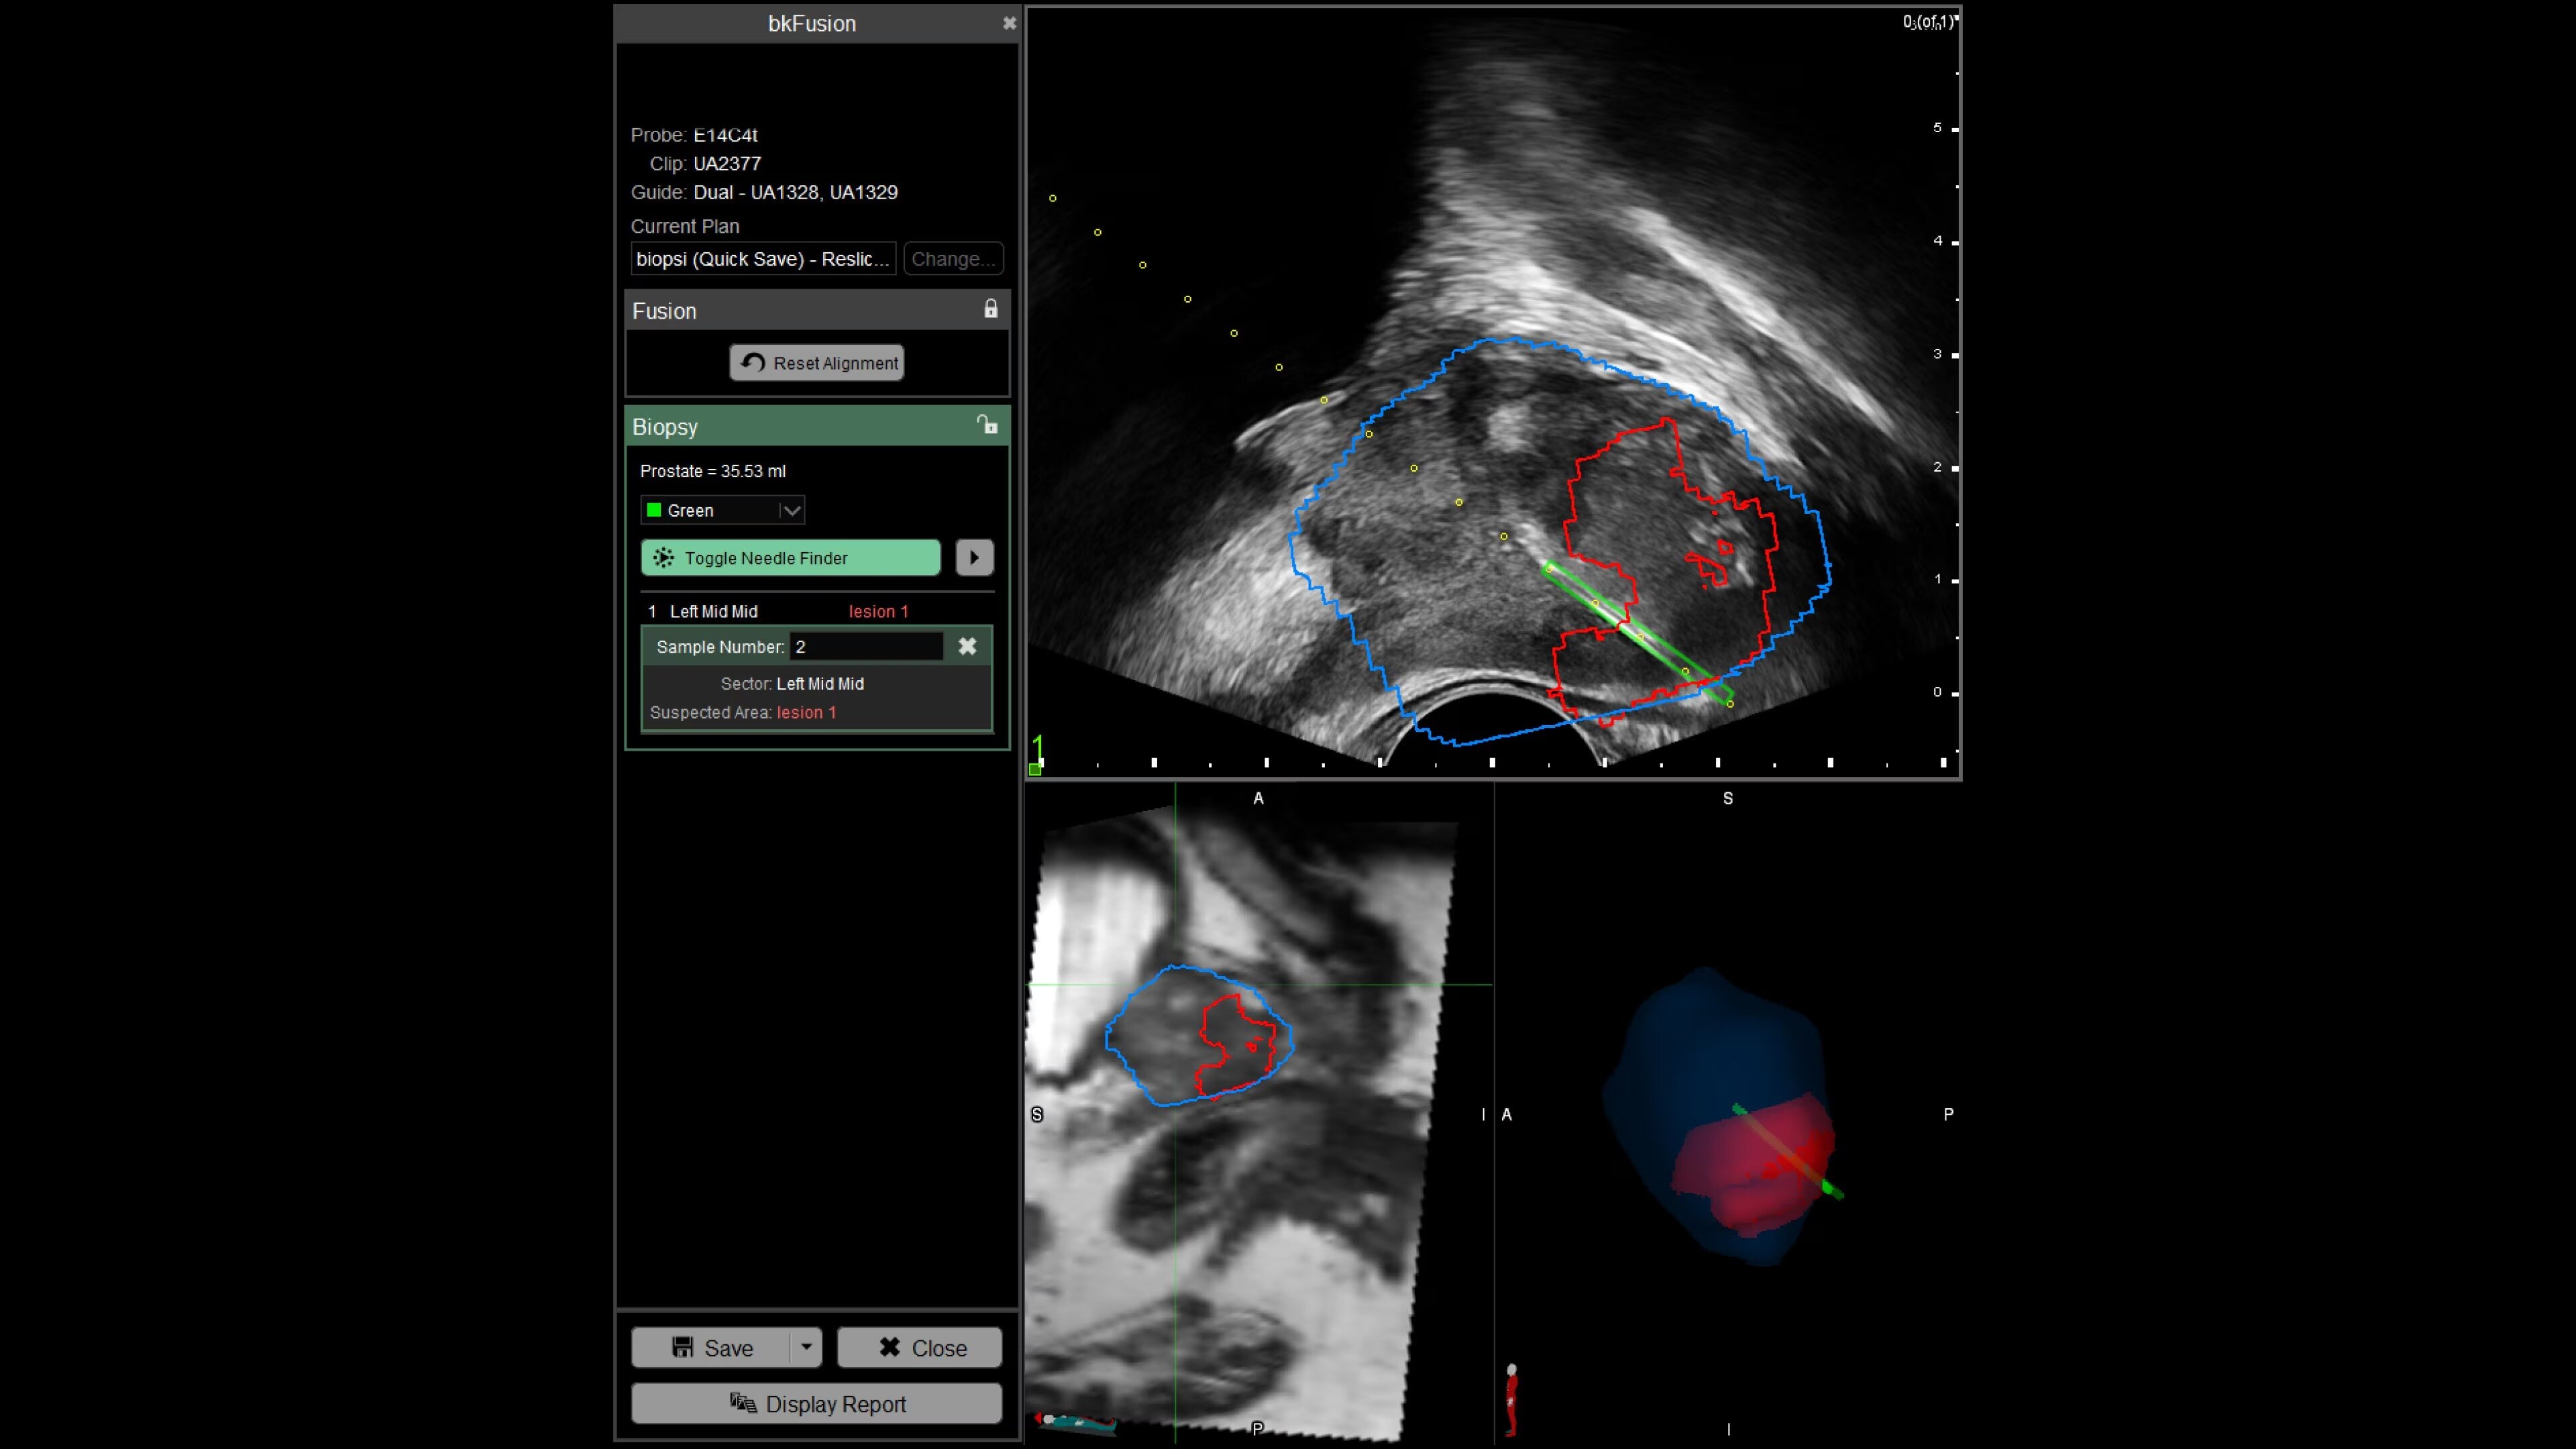

With bkFusion, confidently target your biopsy with clear visualization of organ borders to detect registration errors or deformations in real-time. bkFusion, MRI-ultrasound fusion biopsy solution features proprietary imaging algorithms developed with high spatial, temporal, and contrast resolution for advanced visualization.

bkFusion has proven to accurately detect 84% of PIRADS 3-5 lesions and up to 81% GG>=2 cancer.¹

Enhance biopsy accuracy with Predictive Fusion®

Predictive Fusion® is the proprietary registration method allowing you to imediately see any errors in the overly of MRI and ultrasound images before and during the procedure. Utilizing rigid 2D slice registration, it eliminates distortion in merging 3D shapes, ensuring precise MRI-ultrasound fusion. If changes are needed, make simple, one-touch, micro-adjustments to updte the registration without calibration steps or 3D sweeps. Enhance your prostate biopsy accuracy with this advanced technology.